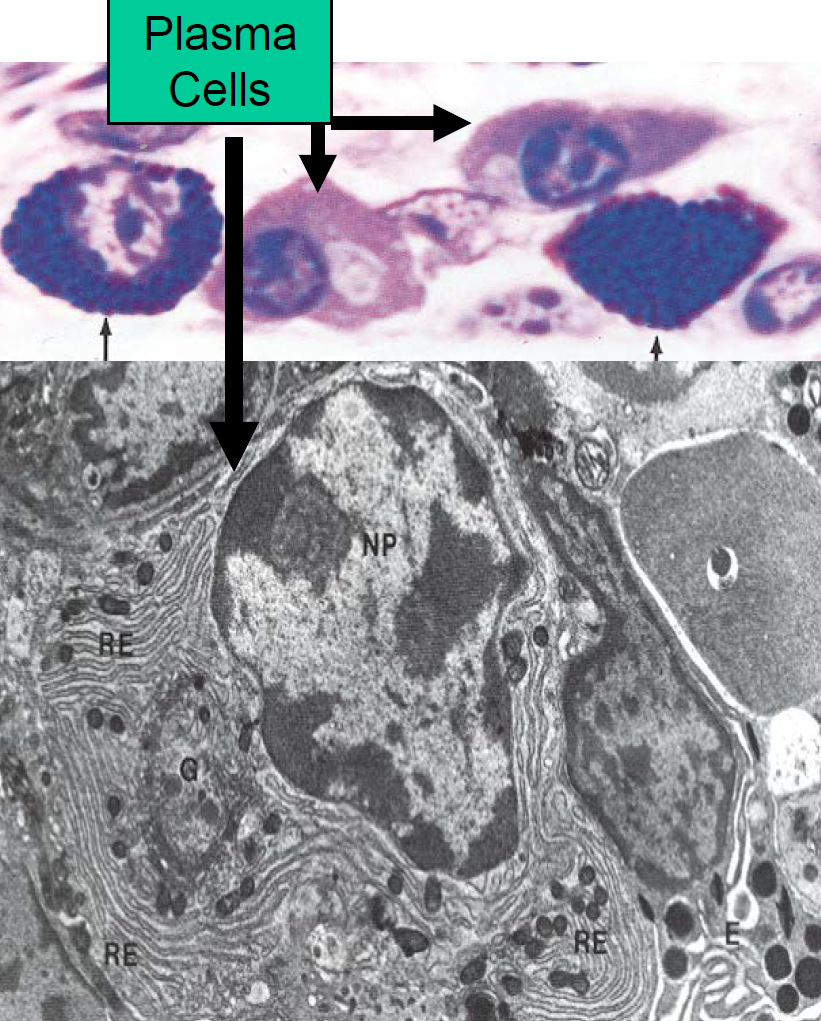

Plasma Cells

What are they differentiated from?

Function?

B-Lymphocytes

Produce antibodies that mediate immunity